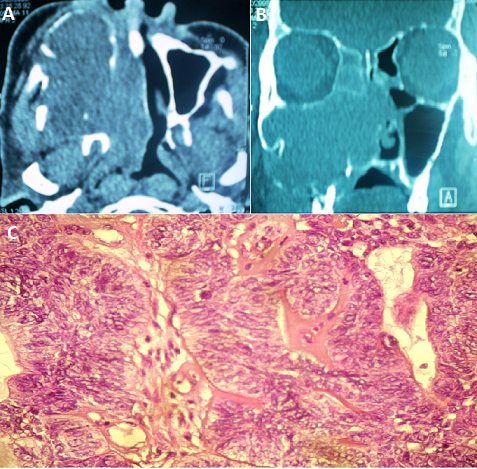

Adenoid cystic carcinomas, formerly known cylindromas, were originally described by Foote and Frozell 1953. These are epithelial malignancies that develop at the expense of salivary glands, other rare localizations have been described in particular in the oral cavity, the sinonasal tract, lacrimal glands or nasopharynx. Clinical and radiological signs are not specific, and are common to all sinonasal tumors, including squamous cell carcinomas and adenocarcinomas. The adequate treatment is surgery, postoperative radiation therapy improves long-term prognosis. These tumors are characterized by aggressiveness and a high incidence of local recurrence and distance metastasis regardless of therapeutic modalities used. We report a case of a 70 year old patient, hospitalized for exploration of a large sinonasal tumors, CT Scann of the face and sinonasal cavities disclosed a large right ethmoïdomaxillonasal tumor, with tissue density with and contrast enhancement, lysing all the walls of the maxillary sinus, septum and the horizontal branch of the mandible. With extension to the infratemporal fossa, the orbital floor, the contralateral nasal cavity, the floor of the nasal cavity and nasopharynx. A nasal biopsy concluded to an adenoid cystic carcinoma, The staging revealed no distant metastases, the tumor was classified T4NoMo.The patient refused any surgery, he was referred for palliative radiotherapy, it was lost sight of.